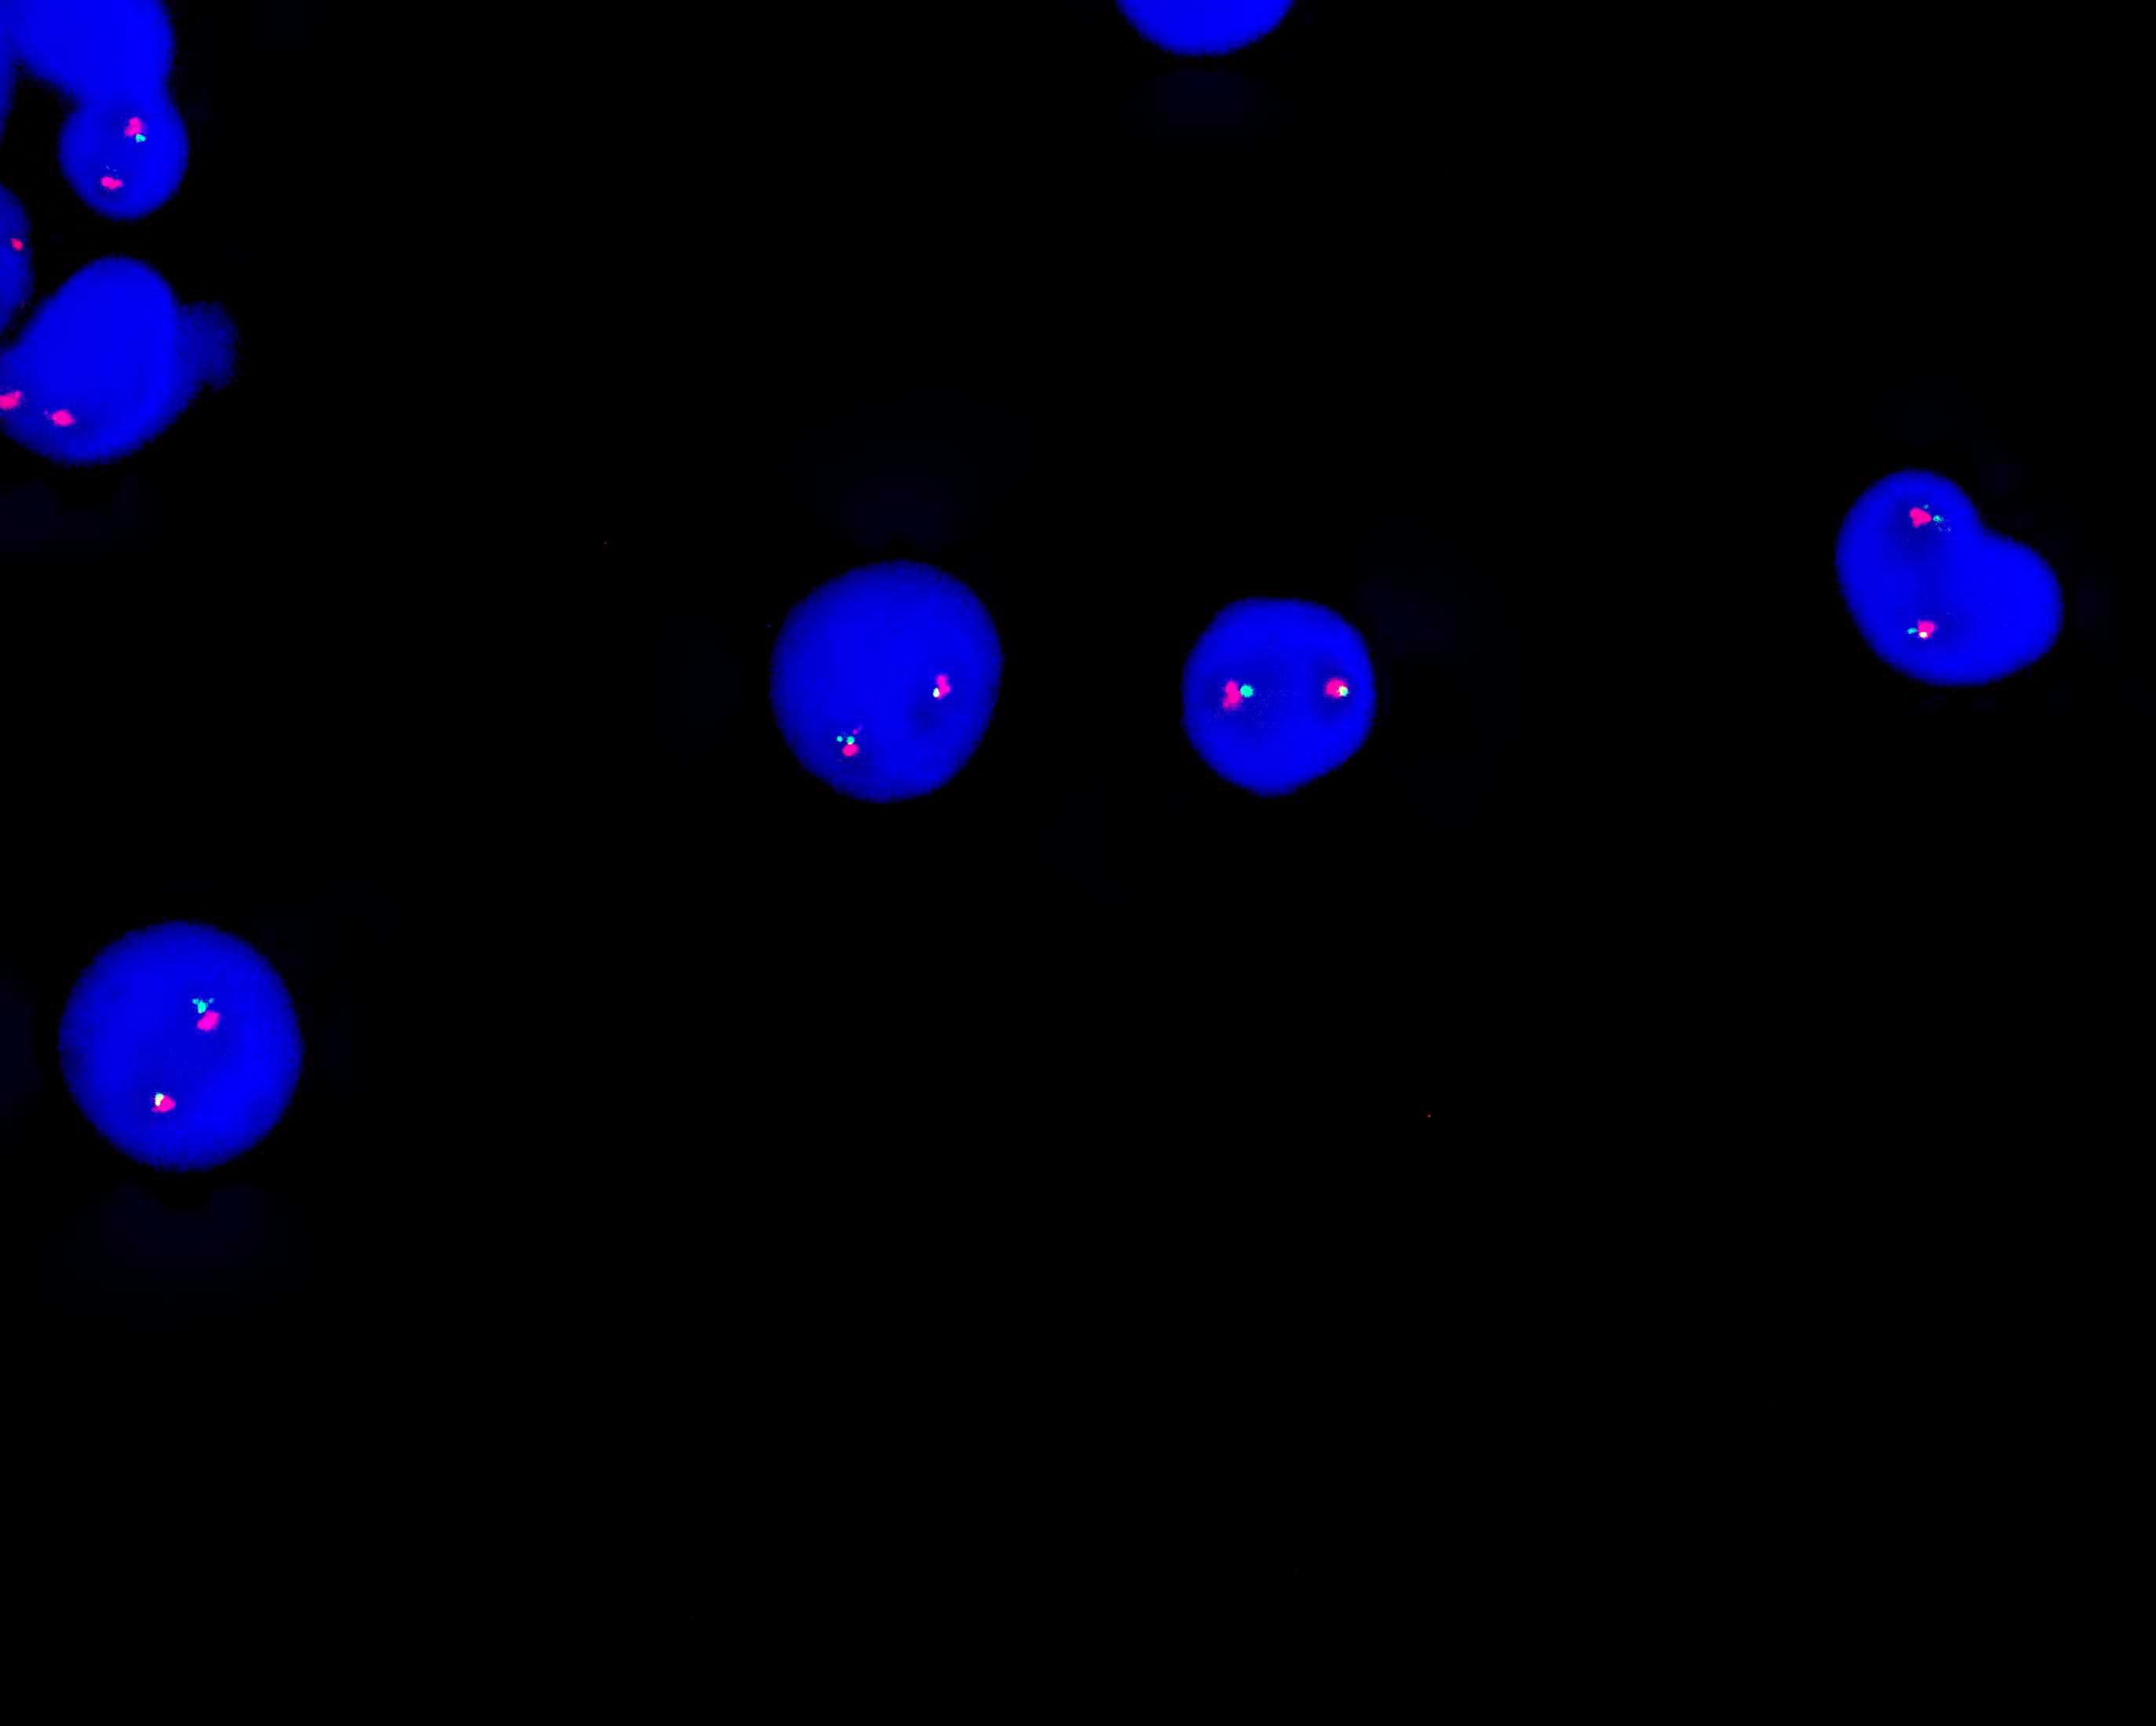

IGH dual color probe

The centromeric end of the IGH gene is labeled orange, with a length of 410 kb; the telomeric end of the IGH gene is labeled green, with a length of 530 kb.